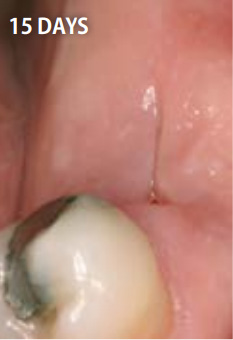

上記の写真はリッジプリザベーションにPRGFを用いたもので、非常に高い効果を得ることができます。

15日後

抜歯してできた穴にPRGFを入れると、上皮や骨の再生が促進され、短期間で抜歯窩がふさがります。また、抜歯後の痛みと腫れも軽減します。

一方、自然治癒を待つ場合には、穴が完全にふさがるまでに数ヶ月かかります。その間にドライソケット(抜歯窩治療不全)になったり、食べ物が詰まるなど、痛みや悪臭を伴うこともあります。